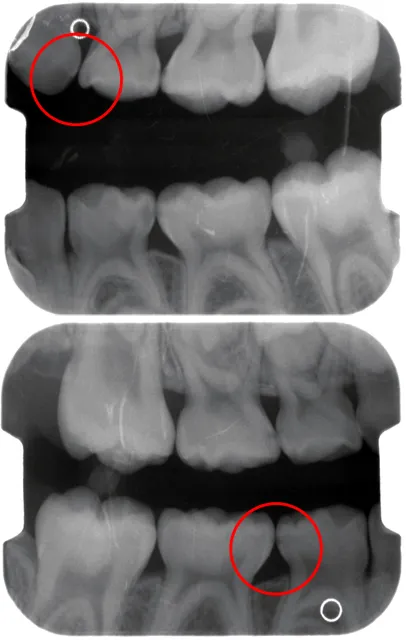

症例:一見カリエスフリー(ムシ歯のない)症例の

ご説明:説明は口腔写真とレントゲンを対比して、2つのモニタで表示した画面を見ながら行います。 また、口腔写真やレントゲン写真は 、画像を印刷してファイリングしてからお渡しするサービスを行っています。